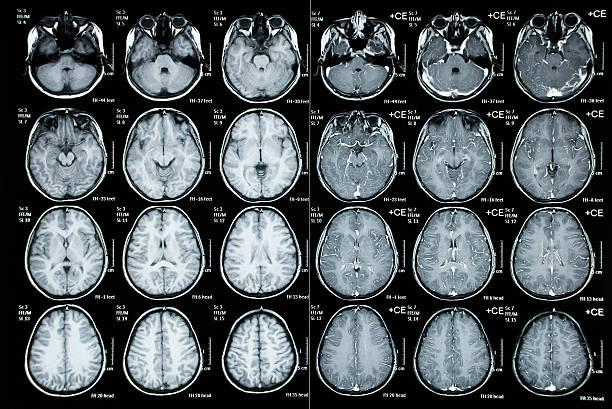

Através desse exame, é possível obter imagens detalhadas da coluna lombar, identificando possíveis lesões, hérnias de disco, compressão nervosa, entre outras condições que afetam a saúde da coluna.

O paciente é posicionado na mesa de exame e, por meio de um equipamento de alta tecnologia, são captadas imagens transversais da região lombar.

Essas imagens são essenciais para o médico radiologista analisar a estrutura da coluna e identificar possíveis alterações que estão causando os sintomas apresentados pelo paciente.